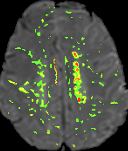

Methods: We included 100 volunteers from GeneSTAR, an ongoing family-based study of families enriched for vascular risk factors and cardiovascular disease, age = 63.3 ± 9.5 years, 60% females, 63% Hypertension, 22% African Americans. Two MRI’s were obtained 10-13 years apart using 3T scanners. At each visit total WMH, PVWMH and DWMH volumes were determined using automated software with consistent co-registration (Figure 1). K2 was measured for each individual by averaging the highest 100 voxels (hotspots) within the regions of interest in each individual lesion using a gadolinium-based DSC-MRI at the second visit (Figure 2). Linear regression models used to analyze the relationship between K2 and volume changes in total WMH, PVWMH, and DWMH, adjusting for age, systolic blood pressure, race, sex, and education.